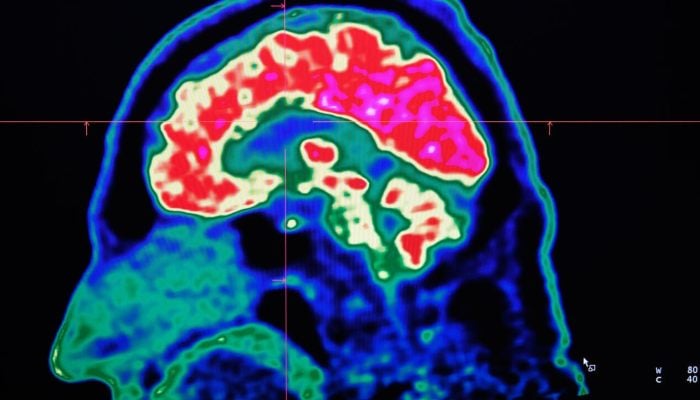

PARIS: Tiny shards of plastic called microplastics have been detected accumulating in human brains, but there is not yet enough evidence to say whether this is doing us harm, experts have said.

These mostly invisible pieces of plastic have been found everywhere from the top of mountains to the bottom of oceans, in the air we breathe and the food we eat. They have also been discovered riddled throughout human bodies, inside lungs, hearts, placentas and even crossing the blood-brain barrier.

The most prominent study looking at microplastics in brains was published in the journal Nature Medicine in February.

The scientists tested brain tissue from 28 people who died in 2016 and 24 who died last year in the US state of New Mexico, finding that the amount of microplastics in the samples increased over time.

There have also been experiments carried out on mice, including a study in Science Advances in January which detected microplastics in their brains.

The Chinese researchers said that microplastics can cause rare blood clots in the brains of mice by obstructing cells — while emphasising that the small mammals are very different to humans.